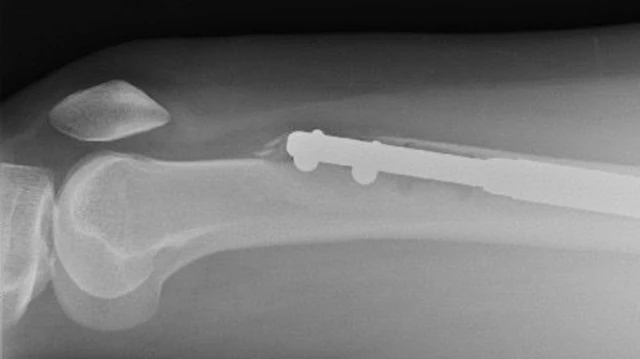

ቀዶ ህክምናው የእግር አጥንቶች ለሁለት ተሰብረው በመካከላቸው የብረት ዘንግ የሚገባበት ሂደት ከመሆኑ ጋር ተያይዞ ህመሙ የሚጠበቅ ነው።

በሁለቱ አጥንቶች መካከል የሚገቡት የብረት ዘንጎች ቀስ በቀስ እንዲራዘሙ ይደረጋል። በዚህም በሁለቱ አጥንቶች መካከል ያለውን ርቀት በማፈራቀቅ ቁመት እንዲጨምር ያደርጋሉ። ለሁለት እንዲሰበሩ የተደረጉት አጥንቶች ቀስ በቀስ ድነውም በመካከላቸው ያለው ክፍተት ተሞልቶ ወጥ ይሆናል።

እሌይን ክሊኒኩ ሄዳ የስካን ምርመራ ተደረገላት። በግራ እግሯ ላይ ያለው አያያዥ ሚስማር ጭኑዋ ላይ ያለው አጥንት ውስጥ ተሰብሯል።

ፊመር የተሰኘው ይህ የጭን አጥንት በሰውነታችን ውስጥ ከሚገኘው ጠንካራው አጥንት ነው።

“ዶክተር ጉይቸት ሚስማሩን በማውጣት ላይ እያለ እንደተሰበረ ነገረኝ። እናም ከሌላ ታካሚ ሌላ ሚስማር ወስደው ማስገባት እንደተቻለ እና የበለጠ ገንዘብ ያስወጣሻል ተባልኩ” ስትል ታስረዳለች።